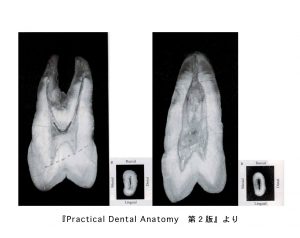

上顎切歯の中身

• 歯の外形を縮小した形を示す。三角形、ロート状、棒状である。

• 根尖側1/3から根尖端に向けて細くなっている。

• 隣接面からみた根管は、唇側面からみた根管より幅広い。

• 根管は根管口から根尖孔までまっすぐとは限らず、根尖付近で少し湾曲している。

下顎切歯の中身

• 歯の外形を縮小した形を示す。細い三角形、ロート状、棒状を示す

• 中央1/3から根尖に向かって著しく細くなっている。

• 隣接面からみた外形は幅広い紡錘形を示す。根管は根管口から中央1/3まで幅広く、根尖側1/3で細くなっている。

• 根尖孔は根尖端とは限らず、根尖孔からそれたところにも開口する。

• 2根管性が20%存在。

上下犬歯の中身

• 歯の外形を縮小した形で、細長い紡錘形を示す。

• 唇側面からみた根管は、歯頸側直下は少し幅広い。

• 隣接面からみると、唇舌径の大きな紡錘形を示し、歯頸側直下で唇舌的に幅広い。